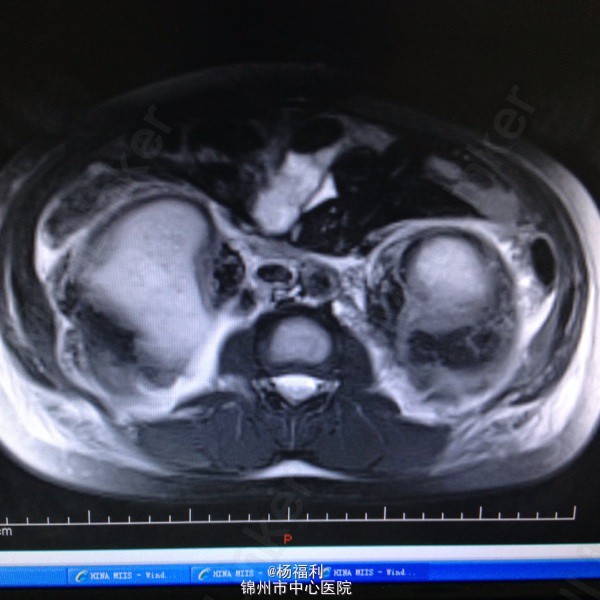

44岁女患。为消化科我会诊患者。 现病史:以上腹痛9小时为主诉入院。无发热及寒战、噁心未呕吐,无腹泻及黑便。 既往史:双眶炎性假瘤2年,口服激素治疗,并补钾。

查体:上腹部压痛,无反跳痛、右侧压痛明显,右肾区叩击痛,左肾区轻叩击痛,双输尿管走形区无压痛。 辅助检查;泌尿系彩超:双肾积水。 血白细胞:9.99*10^9。 肾功能正常。 全腹部ct及MRU检查:见图片。

诊断;真的不知道是啥病。 处理:暂时止痛处理。双肾病变。不知从哪里下手。